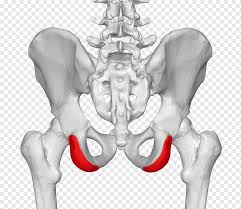

It provides attachment for the inguinal ligament , the sartorius muscle , 1 4 and the tensor fasciae latae muscle. The anterior superior iliac spine (asis) is the most anterior part of the iliac crest. An anterior superior iliac spine (asis) avulsion is a traumatic avulsion of the asis due to a sudden and forceful contraction of the sartorius and tensor fascia lata that occurs in young athletes. Asis, anterior superior iliac spine. This part is the most observable and palpable of the pelvis. The posterior border of the ala, shorter than the anterior, also presents two projections separated by a notch, the posterior superior iliac spine and the posterior inferior iliac spine. Diagnosis is made radiographically with displaced injuries but ct/mri may be required to diagnosis nondisplaced fractures. It provides attachment for the inguinal ligament, and the sartorius muscle. An anterior inferior iliac spine (aiis) avulsion is an apophyseal avulsion injury seen in adolescent athletes as a result of eccentric contraction of the rectus femoris. It refers to the anterior extremity of the iliac crest of the pelvis. The anterior superior iliac spine refers to the anterior extremity of the iliac crest of the pelvis. Outer lip of anterior iliac crest, anterior superior iliac spine (asis) insertion: Classification four types of coccyx have been described:

Outer lip of anterior iliac crest, anterior superior iliac spine (asis) insertion: It provides attachment for the inguinal ligament, and the sartorius muscle. The tensor fasciae latae muscle attaches to the lateral aspect of the superior anterior iliac spine, and also about 5 cm away at the i. Aug 29, 2017 · aiis, anterior inferior iliac spine; Asis, anterior superior iliac spine.

Outer lip of anterior iliac crest, anterior superior iliac spine (asis) insertion: Aug 29, 2017 · aiis, anterior inferior iliac spine; Asis, anterior superior iliac spine. The posterior border of the ala, shorter than the anterior, also presents two projections separated by a notch, the posterior superior iliac spine and the posterior inferior iliac spine. An anterior superior iliac spine (asis) avulsion is a traumatic avulsion of the asis due to a sudden and forceful contraction of the sartorius and tensor fascia lata that occurs in young athletes. The tensor fasciae latae and sartorius muscles of the thigh have their origins at the anterior superior spine. An anterior inferior iliac spine (aiis) avulsion is an apophyseal avulsion injury seen in adolescent athletes as a result of eccentric contraction of the rectus femoris. It provides attachment for the inguinal ligament, and the sartorius muscle. The posterior superior iliac spine serves for the attachment of the oblique portion of the posterior sacroiliac ligaments and the multifidus. It provides attachment for the inguinal ligament , the sartorius muscle , 1 4 and the tensor fasciae latae muscle. It can be palpated by putting the hands at the top of the hipbones and following the bony margins toward the front of the hips. Classification four types of coccyx have been described: Diagnosis is made radiographically with displaced injuries but ct/mri may be required to diagnosis nondisplaced fractures.

The blog post articles in this. Outer lip of anterior iliac crest, anterior superior iliac spine (asis) insertion: The anterior superior iliac spine is a bony projection of the iliac bone, and an important landmark of surface anatomy. The tensor fasciae latae muscle attaches to the lateral aspect of the superior anterior iliac spine, and also about 5 cm away at the i. Thigh abduction, thigh internal rotation (anterior part);